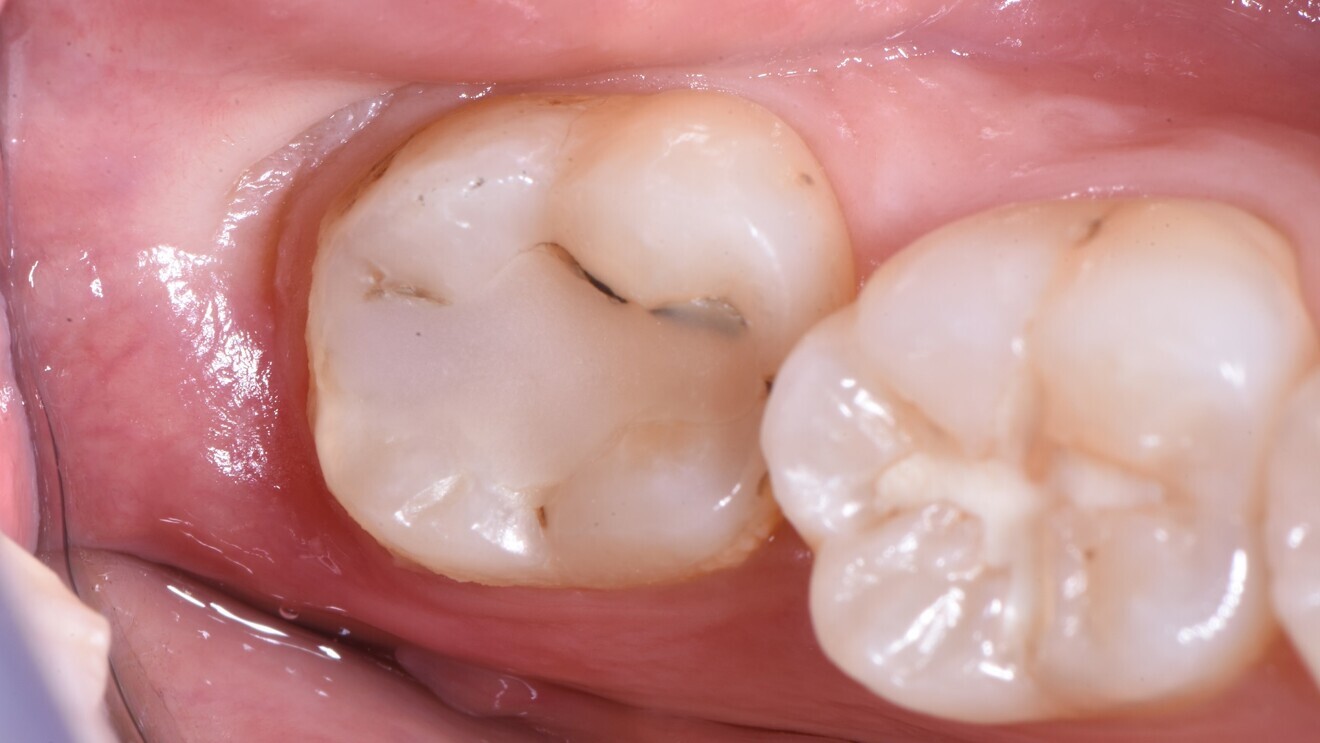

Fig. 1: Multiple cervical non-carious lesions prior to treatment. (All images courtesy of Dr Matteo Basso, Italy)

Cervical lesions (Figs. 1–3)

The cervical placement of glass ionomers, especially resin-modified glass ionomers, has a long tradition and is backed by a wealth of clinical studies demonstrating the usefulness of this material for this purpose. Resin-modified glass ionomers have consistently outperformed alternative materials when it comes to survival and success of cervical restorations.5 For glass hybrids, two randomised trials comparing this material against resin composites were identified.